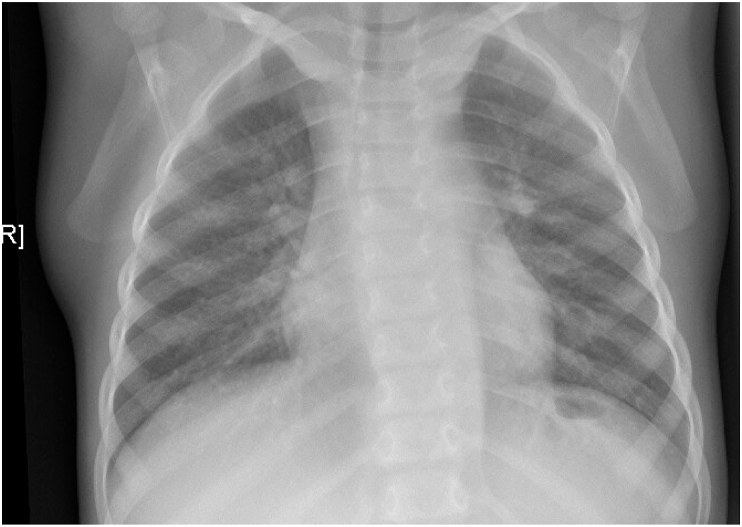

A two-year old girl was presented in our pediatric infectious disease unit for evaluation of tuberculosis (TB) in the context of contact tracing. She was previously diagnosed with neurofibromatosis type 1 (NF1). Chest X-ray (CXR) revealed a mediastinal and hilar mass indicating lymphadenopathy (Fig. 1). However, tuberculin skin test (TST; PPD-RT23; AJ Vaccines A/S, Denmark) and Interferon-Gamma-Release Assay (IGRA; QuantiFERON®-TB Gold; Qiagen, Hilden, Germany) were negative. Furthermore, she had no clinical symptoms of TB. Due to the preexisting disease, magnetic resonance imaging (MRI) was performed, which showed a large, confluent plexiform cervical and thoracic neurofibroma (Fig. 2). Neither enlarged hilar or mediastinal lymph nodes nor other signs of intrathoracic tuberculosis were detectable. The child was examined again eight weeks after the last contact to the TB source case. TST and IGRA remained negative in the asymptomatic child and TB could therefore be virtually excluded.

Fig. 1.

CXR shows an chimney-shaped opacity in the upper mediastinum, the hilus region is rounded. The trachea is shifted to the left side and impressed. The lung parenchyma shows no pathologies. There are no calcifications or apical infiltrates.